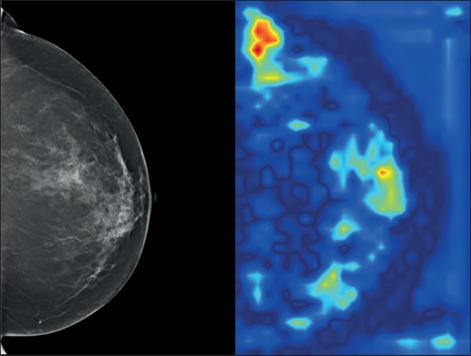

Artificial intelligence (AI) has the potential to revolutionize mammography and transform breast cancer screening. With the advancements in AI, mammography images can be analyzed more accurately and quickly, leading to improved diagnosis and treatment. AI algorithms can help identify subtle changes in breast tissue that may indicate cancer, leading to earlier detection and better outcomes for patients. AI-powered mammography systems can also assist radiologists in making more informed decisions by providing them with relevant information and highlighting potential areas of concern.

In the future, AI in mammography is expected to become even more sophisticated, with the ability to analyze multi-modal imaging data and incorporate patient history and risk factors into the analysis. This could lead to a more personalized approach to breast cancer screening, with tailored recommendations for each patient based on their individual risk profile. The use of AI in mammography has the potential to save lives by improving the accuracy and efficiency of breast cancer detection, and it is an exciting area of development for the healthcare industry.